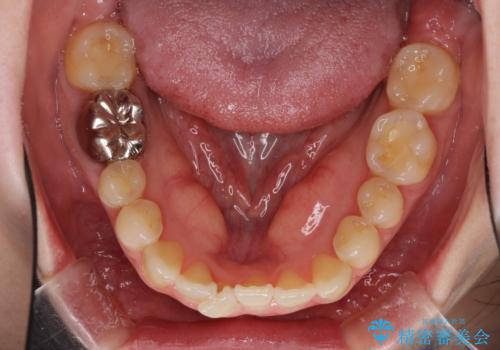

- 前歯のデコボコを治したいとのことで来院された患者様です。

上下顎ともに歯列全体の後方移動とIPR(歯と歯の間を削る)によってデコボコが解消するように設計し、インビザラインにより治療を行うこととしました。

1日22時間の装着時間をほとんど達成することができず、治療には当初予定の2倍以上の期間を要することとなりました。